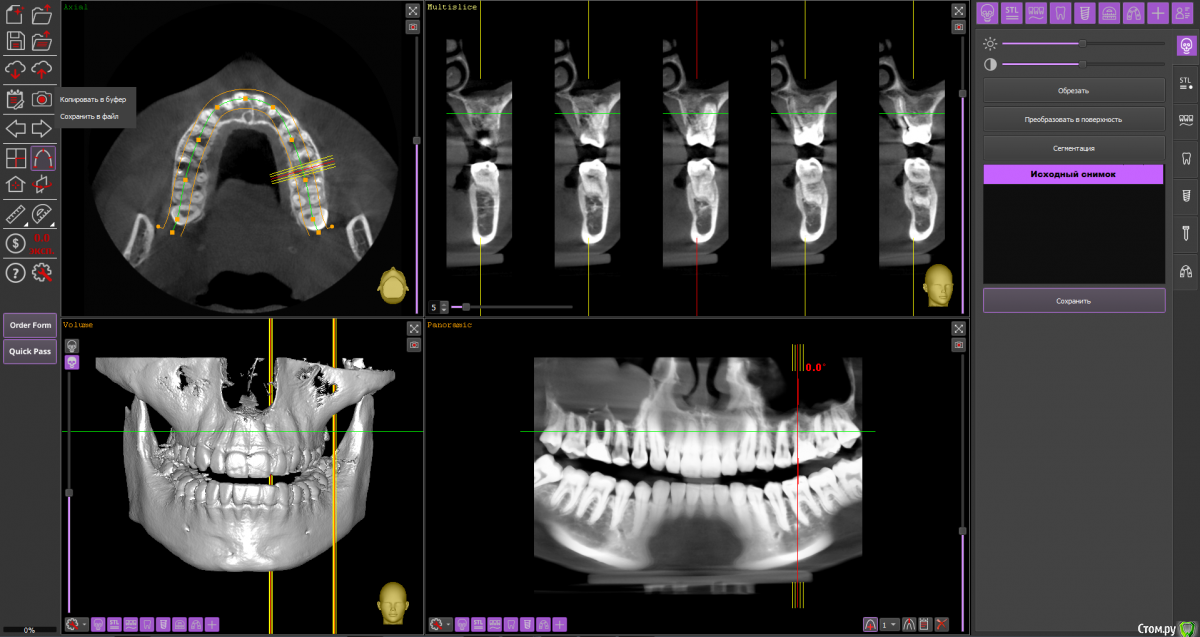

Ольга Вовк Опубликовано 10 февраля, 2021 Поделиться Опубликовано 10 февраля, 2021 Добрый день! Очень прошу помочь по таким вопросам:1. Верхняя шестерка справа - там киста перешедшая в гайморову пазуху (узнала это 4 месяца назад). Зуб ныл 2 года назад, тогда врач просто прописала Аугментин. Все прошло, но опять начал поднывать неделю назад (сейчас опять прошло). Была на консультации, сказали вырывать и прочищать пазуху нужно сейчас, и по приезду уже дальше разбираться. Как лучше быть, если я через неделю уезжаю на 4.5 месяца в страну, где никак не смогу продолжить лечение, а значит ставлю на паузу все на этот период.1. Удалить зуб сейчас, чтоб он зажил и через 4.5 месяца приехав сделать синус лифтинг и ставить имплант, или же ждать это время не удаляя зуб? 2. Не разрушится ли если сейчас не вырвать полностью костная ткань? 3. Можно ли не ставить имлпант, а сдвинуть 7 и 8 зуб к 5ому? Также вопрос по верхней шестерке слева - можно ли ее перелечить под микроскопом, или нужно делать резекцию? Разные врачи сделали разные выводы по нему Ссылка на архив файлов панорамного КТ - http://fayloobmennik.cloud/7414975 Спасибо вам, очень надеюсь на совет Ссылка на комментарий

Ольга Вовк Опубликовано 10 февраля, 2021 Автор Поделиться Опубликовано 10 февраля, 2021 16_1.png 16_2.png 16_3.png 26_1.png 26_2.png 26_3.png 26_4.png Зуб 16, мне кажется, лучше удалить до отъезда. Насчёт ортодонтического перемещения 8-го и 7-го на место 6-го, необходимо с ортодонтом очно пообщаться, но на мой взгляд, хирургическое лечение будет более предсказуемым.Зуб 26 может оказаться непростым для эндодонтиста, но если доктор берётся и Вы ему доверяете, то начать стоит с повторного эндодонтического лечения с увеличением.Спасибо вам огромное! Я так понимаю, что если не удалить сейчас, то тогда к приезду (3 июля) уже совсем костной ткани не останется? Просто если сейчас удалить и будут осложнения, или соустье в гайморову, то я уеду и там не знаю что буду делать в такой ситуации(( Ссылка на комментарий